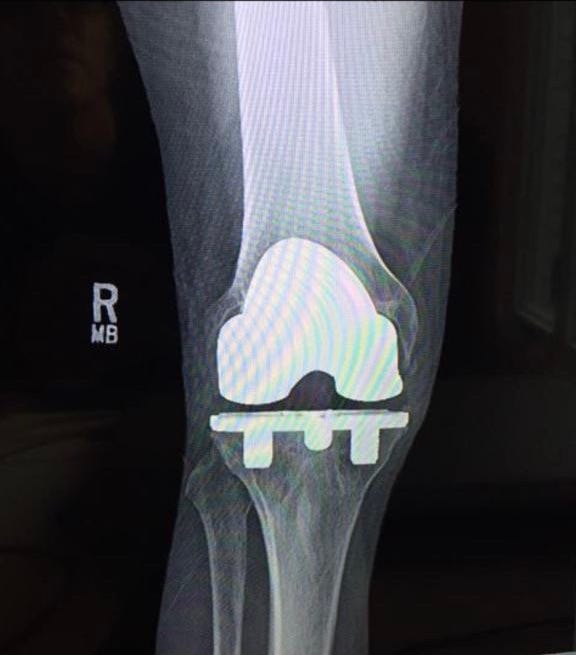

At 46, I had to have my right knee replaced with a titanium knee.

Recovering from that huge intervention, where the doctor rips out your knee and chisels away at your bones to cement the new knee together, was a brutally painful challenge.

Going that far in professional sports is hard and takes its toll — thus, the injured knee. But it gave me deep knowledge of sports and how or not to train.